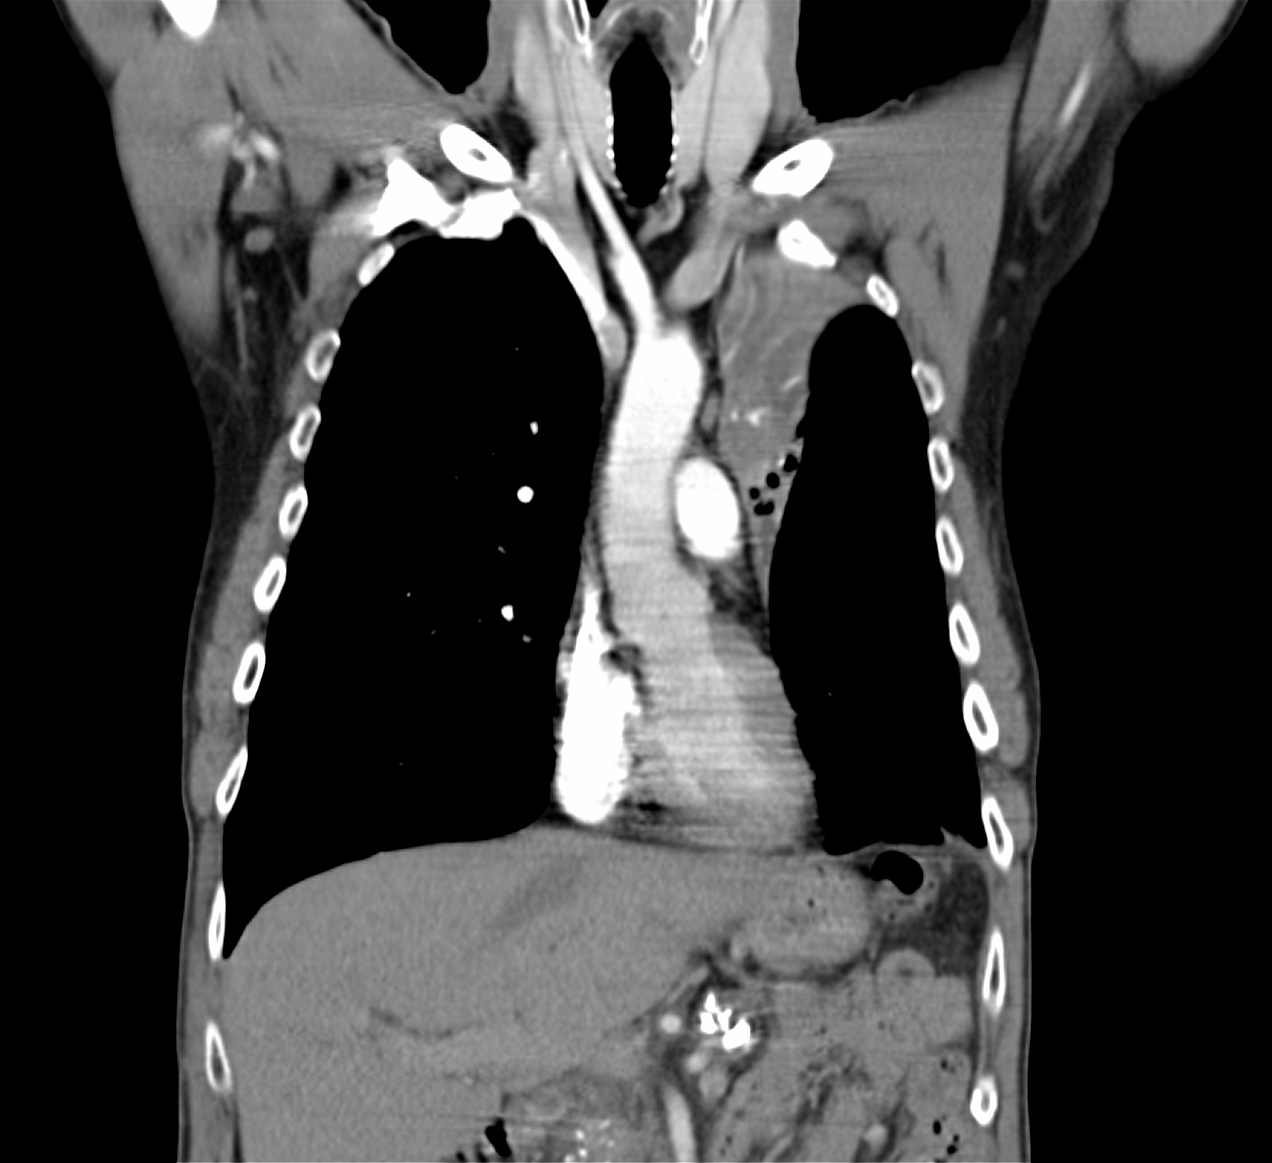

22. Central lung tumor with mediastinal lymphadenopathy. CT coronal and sagittal reconstructions.

70 year old man, COPD, hoarse. Right hilar mass, bronchoscopy was negative.

The larynx is rotated to the right, no motion of the right side of the larynx can be observed, swollen left plica ventricularis area.

CT: 13x11 mm large nodular mass in the left 10th segment. Bilateral hilar lymphadenomegaly with central hypodensity. A 34x21 mm large lymph node conglomeration can be observed in subcarinal location (peripheral contrast enhancement). Lymphadenopathy in the aortopulmonary window (15 mm large), and a 26 mm large lymph node can be observed in paraaortic location above the trachea bifurcation which has an esophagus-compressing effect. In the superior chest aperture there is a 38x28 large fused lymph node conglomerate which causes the left shift of the esophagus and trachea.